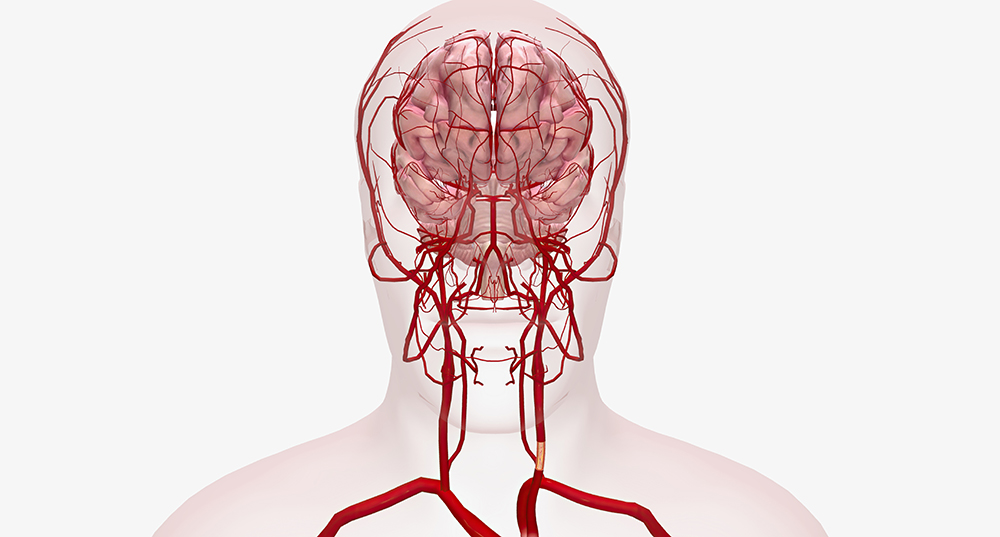

모야모야병은 뇌의 주요 혈관, 특히 내경동맥과 이를 따라 뻗어 있는 뇌혈관이 점차 좁아지면서 비정상적인 혈관이 생기는 질환입니다. 이러한 비정상 혈관은 뇌로 가는 혈류를 보충하려는 대체 혈관 역할을 하지만, 쉽게 파열되거나 혈류가 부족해지는 문제를 일으킵니다.

‘모야모야’는 일본어로 ‘뿌옇게 보인다’는 뜻으로, 뇌혈관 조영술에서 혈관이 비정상적으로 얇아져 희미하게 보이는 것을 비유한 이름입니다. 이 병은 유병률이 비교적 낮지만, 동아시아에서 특히 많이 나타나는 것으로 보고됩니다.